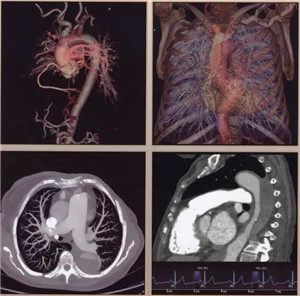

扫描范围最大:16厘米宽体宝石探测器,心脏、颅脑、肝脏等单器官检查一次扫描就可实现全覆盖;

扫描速度超快:仅需0.28秒,不受心率快慢限制,只需一个心跳即完成精准的心脏CT检查,成为无创确诊冠心病的最佳检查手段。